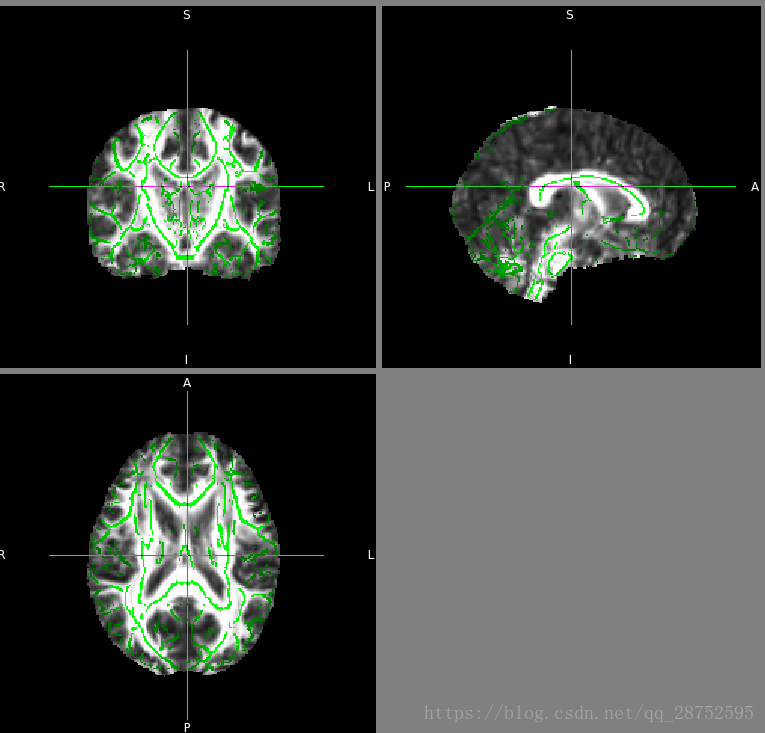

将4D FA数据和骨架加载到FSLView中:

cd stats fslview_deprecated all_FA -b 0,0.8 mean_FA_skeleton -b 0.2,0.8 -l Green

4.在所选阈值处对平均FA骨架图像进行阈值处理 - 效果良好的常见值为0.2

tbss_4_prestats 0.2